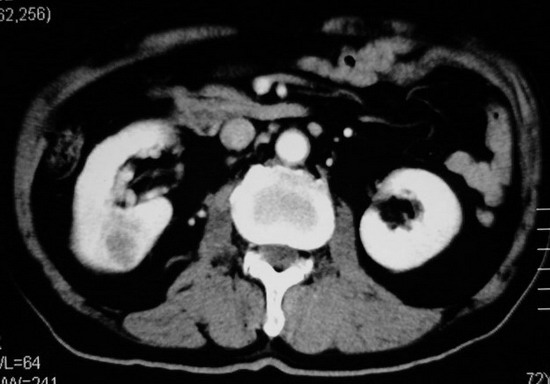

以下是引用杀毒软件在2008-11-17 19:15:00的发言:[br]考虑------右肾癌合并肾静脉---同侧肾上腺受侵可能性大

以下是引用zjzjr在2008-11-17 20:45:00的发言:[br]考虑------右肾癌合并肾静脉---同侧肾上腺受侵可能性大及腹膜后淋巴结转移.